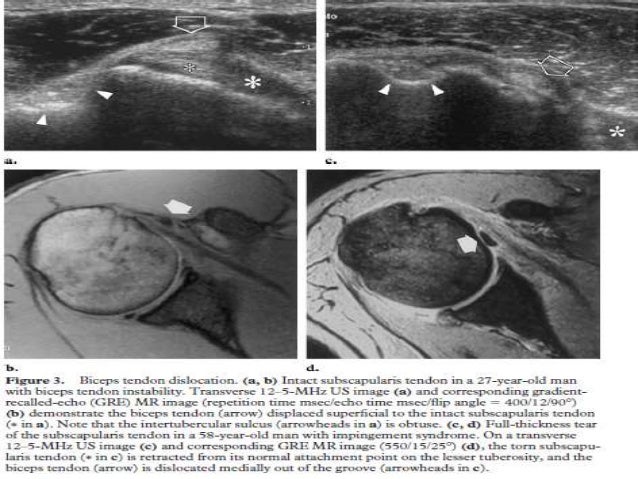

45. 45. Biceps tendon subluxation. Transverse scan through the left BG shows an empty groove. Note that the groove in this patient is shallow. The biceps tendon (arrow) lies medially, anterior to the lesser tuberosity of the humerus. A small amount of fluid is seen in the tendon sheath.